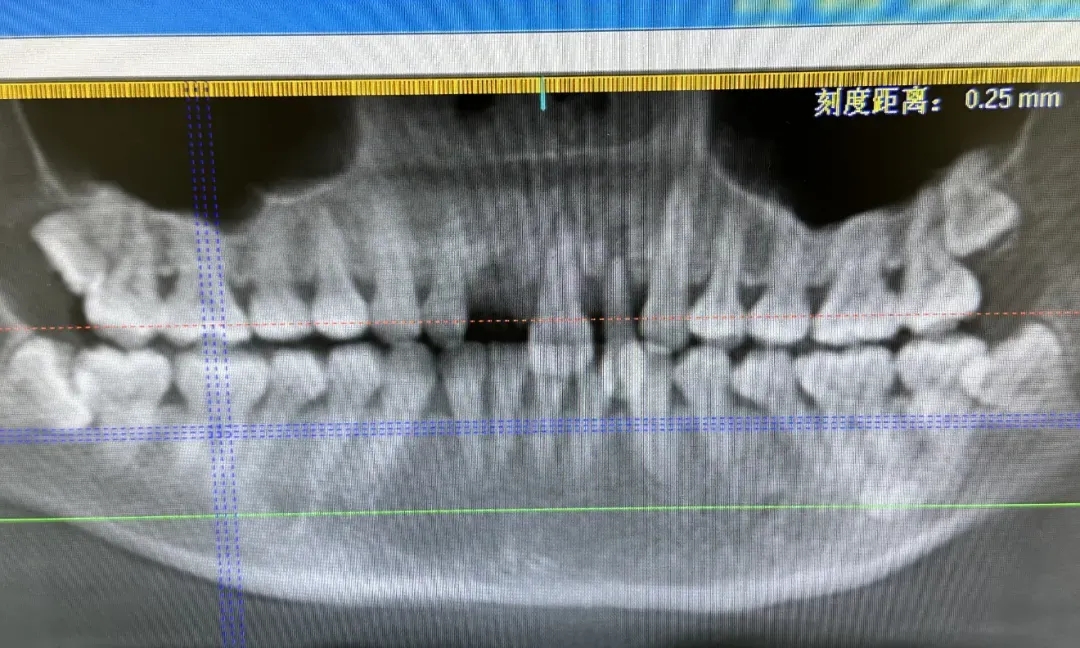

杭州萧山区第一人民医院口腔科因夜骑受伤到急诊就诊的患者不少,严重的甚至摔掉了三颗门牙。

她曾接诊过一位女骑友,因为车轮细,骑行时不慎卡进马路缝隙里,倒地后因剧烈的冲击导致三颗门牙全部脱位。

幸运的是,门牙相对比较完整,在该骑友拿着两颗门牙到医院后,田琪琪和助手当即就将门牙进行复位固定,“还有一颗牙落在了现场,我们赶紧让她的同伴回去找,还好找着了,当晚就把牙齿全部进行结扎固定,加上后续的治疗,她现在恢复得不错。”